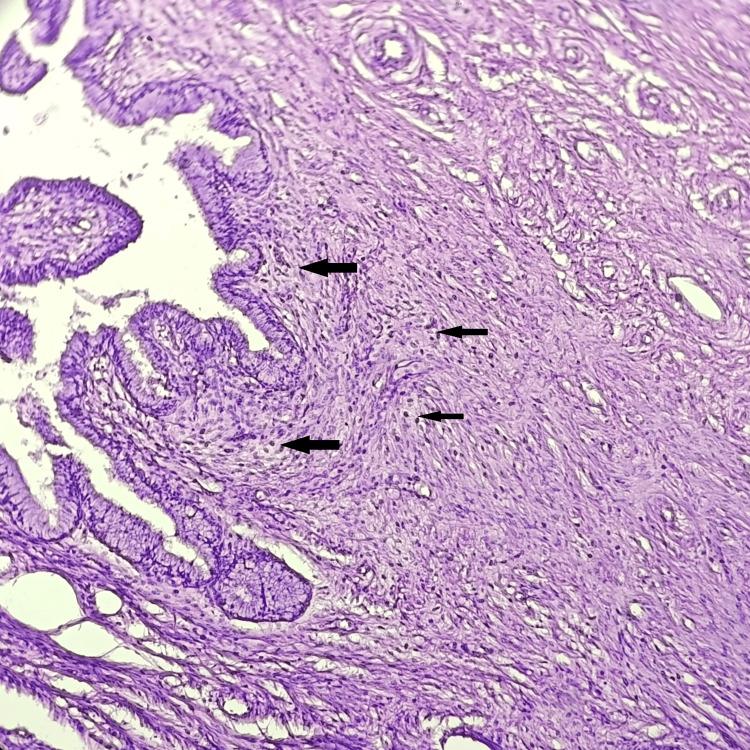

Introduction The uterus is a crucial reproductive organ that is susceptible to the development of several non-neoplastic and neoplastic diseases in women, greatly increasing morbidity and mortality. Although there are various therapeutic options, hysterectomy is still a popular treatment option throughout the world. Abnormal uterine bleeding, pelvic pain, pelvic inflammatory disease (PID), prolapse of the uterus, adenomyosis, endometriosis, fibroids, gynecological malignancies, and obstetric problems that require hysterectomy, all samples must be examined histopathologically. Histopathological examination of the specimens obtained after hysterectomy is important for both diagnosis and treatment. The current work aimed to identify the various clinical indications, analyze the clinicopathological correlation in hysterectomy specimens, and analyze the patterns of lesions in hysterectomy specimens. Materials and methods This study was conducted in the Department of Pathology at the Datta Meghe Medical College, Wanadongari, Nagpur, from February 2022 to January 2023. All types of hysterectomy specimens received during this year were examined, and the tissues were processed and stained with H&E. Histopathological examination was performed, and various lesions in the hysterectomy specimens were examined. The study included all forms of hysterectomy, including abdominal, vaginal, laparoscopic, and total abdominal hysterectomy. Results An analysis of 110 cases of hysterectomy revealed that abdominal hysterectomy was the type of hysterectomy in 79 (71.82%) cases, with a maximum age range of 35 to 45 years (42.72%). The proliferative phase endometrium was the most common endometrial pathology, accounting for 43 (39.09%) cases, followed by the atrophic endometrium in 35 (31.82%) cases. Leiomyoma was the most prevalent myometrial lesion, accounting for 52 (47.28%) cases, followed by adenomyosis, accounting for 23 (20.91%) cases. Chronic cervicitis was the most common incidental finding in the hysterectomy samples, accounting for 85 (77.28%) cases. Follicular cysts, representing 22 (20%) cases, were the most common ovarian lesions, followed by serous cystadenoma in seven (6.37%) cases. Two cases of malignant tumors were noted: one case of endometrial carcinoma and one case of mucinous cystadenocarcinoma of the ovary. In most cases, ranging from 70% to 100%, the final histopathological diagnosis supports the preoperative clinical diagnosis. Conclusion Hysterectomy is the most common major gynecological surgery performed under elective conditions. Although histological studies and clinical diagnoses are closely correlated, several lesions, including chronic cervicitis and adenomyosis, were discovered incidentally. Therefore, every hysterectomy specimen must undergo a thorough histological investigation, even if it appears superficially normal, to confirm the diagnosis and improve postoperative care.

对110例子宫切除术病例的分析显示,79例(71.82%)为腹部子宫切除术,最大年龄范围为35至45岁(42.72%)。增殖期子宫内膜是最常见的子宫内膜病理类型,占43例(39.09%),其次是萎缩性子宫内膜35例(31.82%)。平滑肌瘤是最常见的肌层病变,占52例(47.28%),其次是子宫腺肌病,占23例(20.91%)。慢性宫颈炎是子宫切除标本中最常见的偶然发现,占85例(77.28%)。滤泡囊肿占22例(20%),是最常见的卵巢病变,其次是浆液性囊腺瘤7例(6.37%)。发现2例恶性肿瘤:1例子宫内膜癌和1例卵巢黏液性囊腺癌。在大多数情况下,从70%到100%,最终的组织病理学诊断支持术前临床诊断。